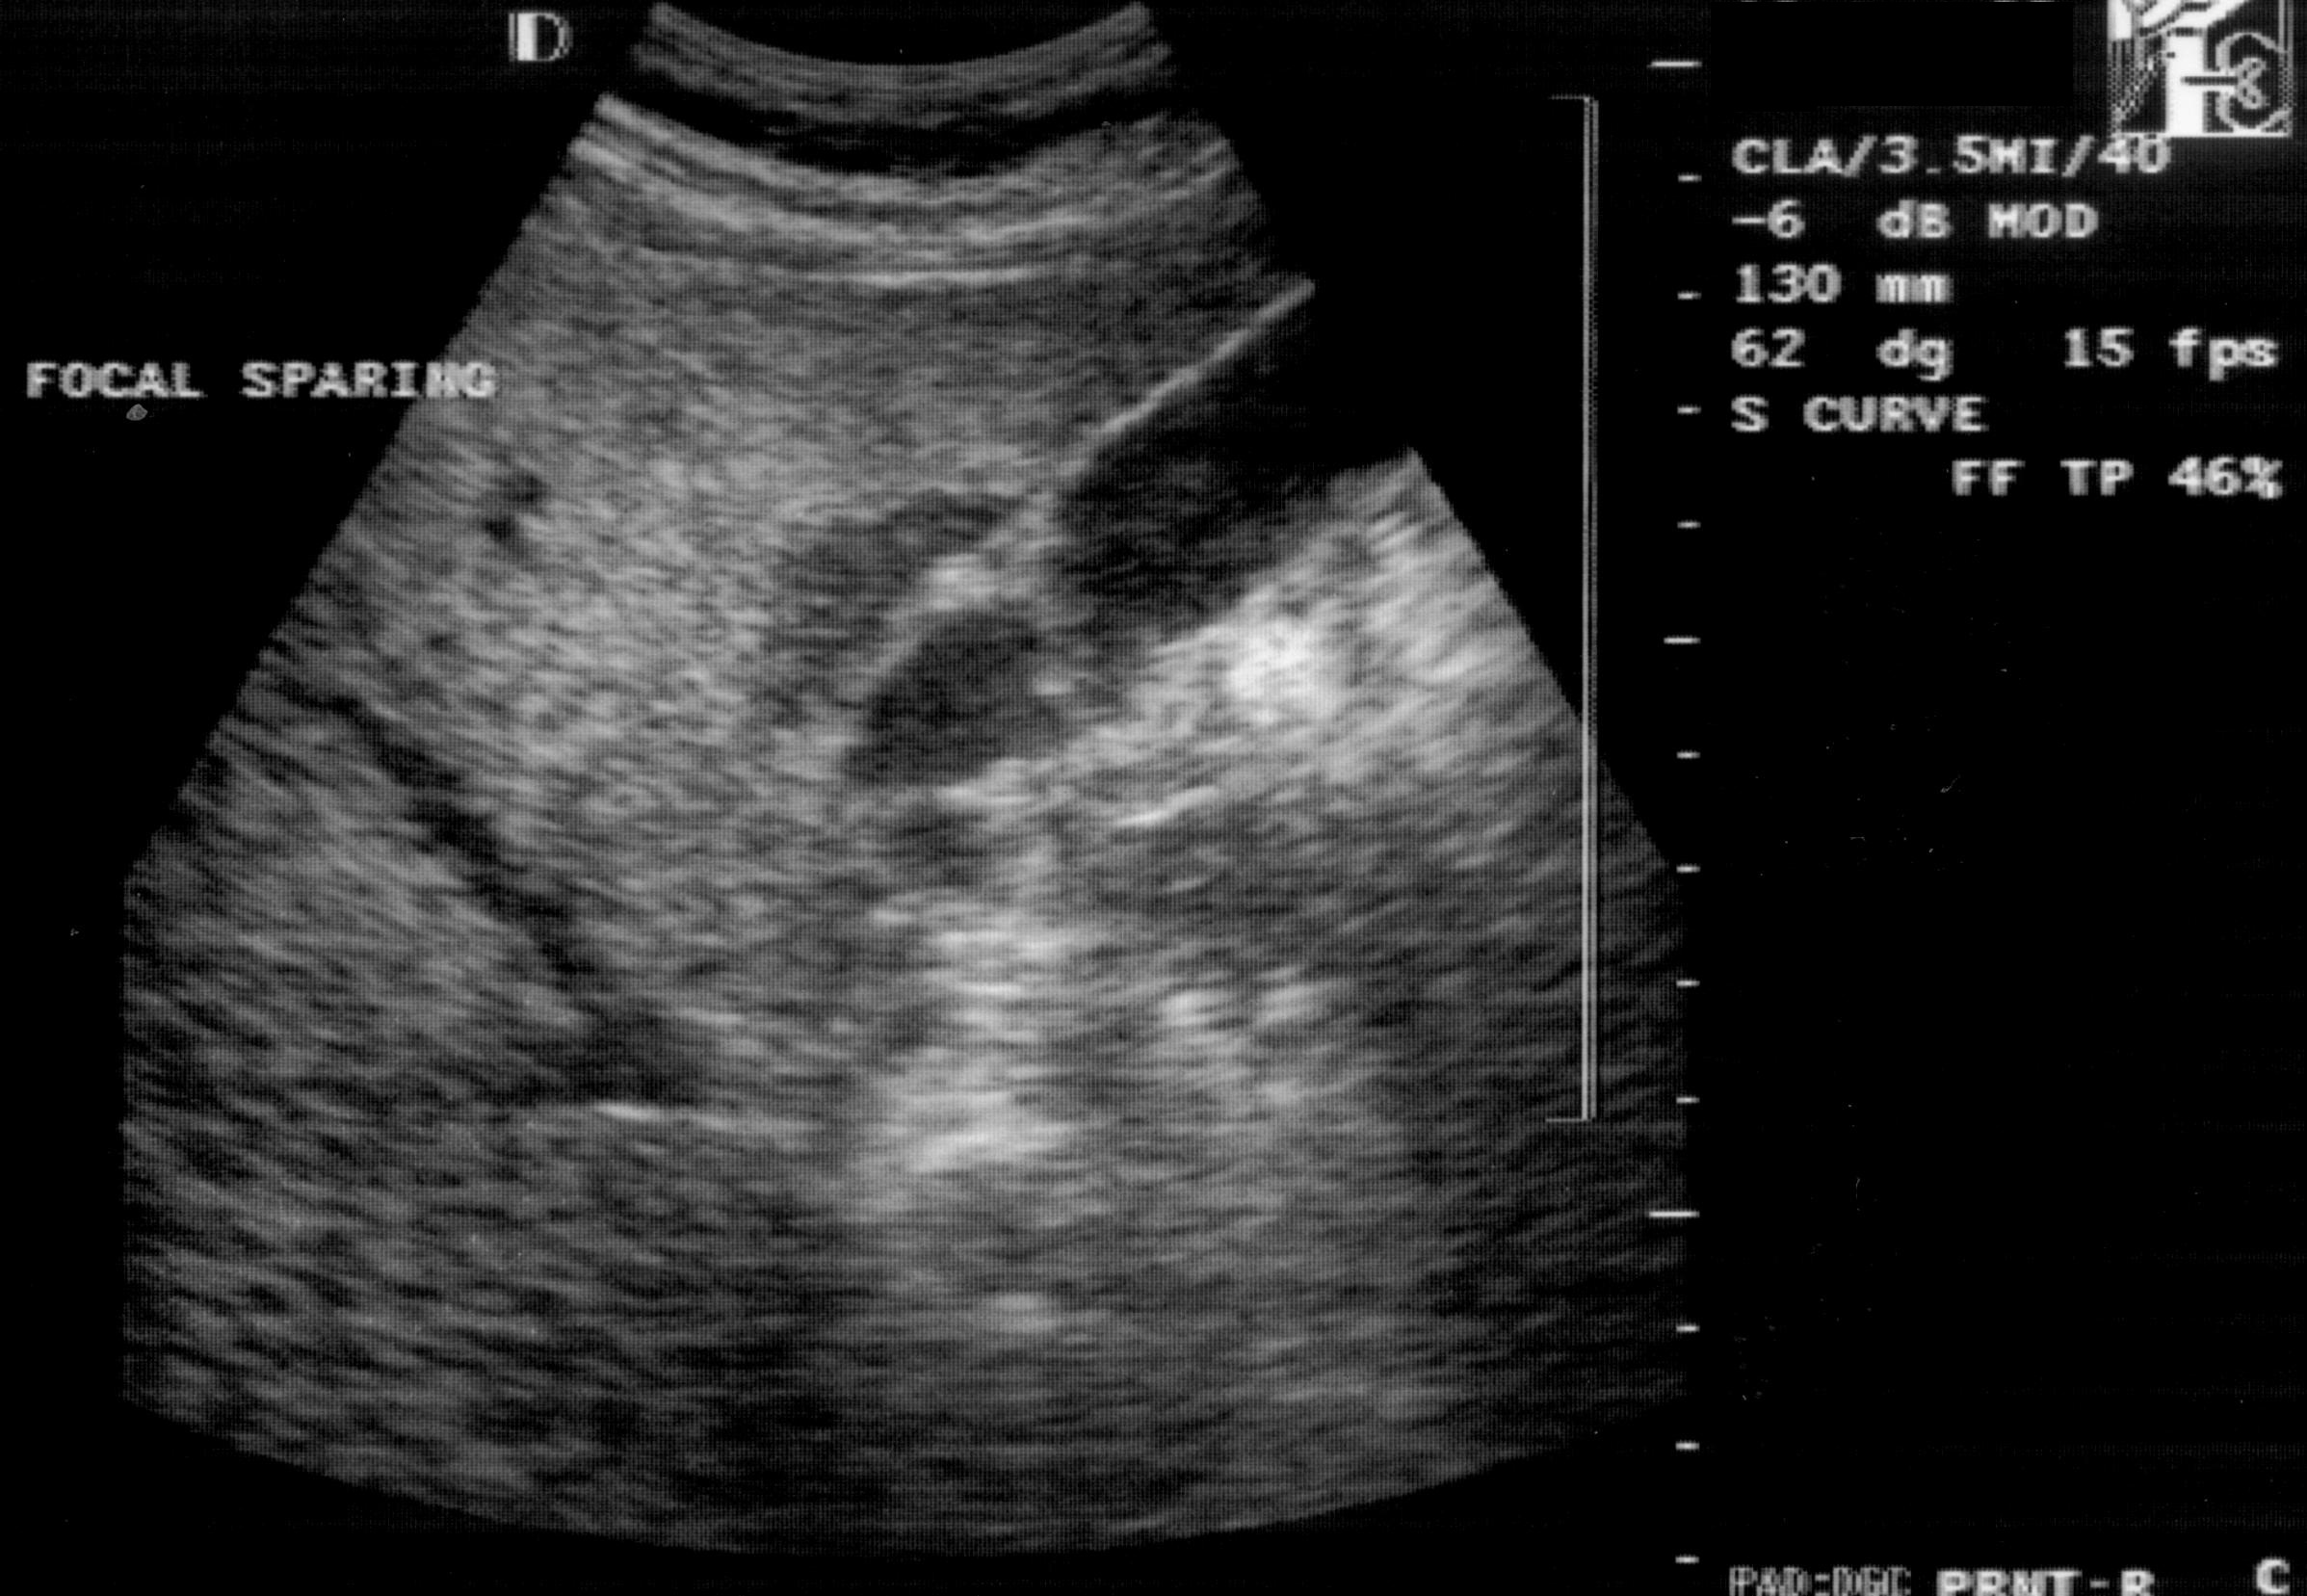

The focal forms develop due to the different perfusion statuses. It is characterized by no space occupying effect (no vessel displacement), and their appearence can change significantly during the check-up examinations. In the areas of decreased portal circulation (eg., ventral to the portal vein, next to the gallbladder) less fat is deposited, this area appears focally hypoechoic - focal sparing (Figure 13). In case of focal deposition, round, nodular or girland (chart-like) hyperechoic infiltration areas develop in the intact liver.

Figure 13: Focal sparing next to the gallbladder